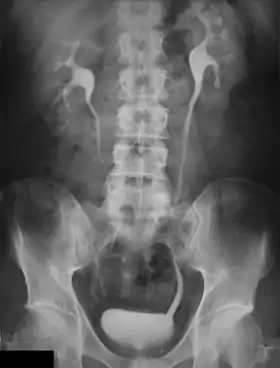

An intravenous pyelogram (IVP), also called an intravenous urogram (IVU), is a radiological procedure used to visualize abnormalities of the urinary system, including the kidneys, ureters, and bladder. Unlike a kidneys, ureters, and bladder x-ray (KUB), which is a plain (that is, noncontrast) radiograph, an IVP uses contrast to highlight the urinary tract.

In IVP, the contrast agent is given through a vein (intravenously), allowed to be cleared by the kidneys and excreted through the urinary tract as part of the urine.[5] If this is contraindicated for some reason, a retrograde pyelogram, with the contrast flowing upstream, can be done instead.

An injection of X-ray contrast medium is given to a patient via a needle or cannula into the vein,[7] typically in the antecubital fossa of arm. The contrast is excreted or removed from the bloodstream via the kidneys, and the contrast media becomes visible on X-rays almost immediately after injection. X-rays are taken at specific time intervals to capture the contrast as it travels through the different parts of the urinary system.[7] At the end of the test, a person is asked to pass urine and a final X-ray is taken.[7]

Immediately after the contrast is administered, it appears on an X-ray as a 'renal blush'. This is the contrast being filtered through the cortex. At an interval of 3 minutes, the renal blush is still evident (to a lesser extent) but the calyces and renal pelvis are now visible. At 9 to 13 minutes the contrast begins to empty into the ureters and travel to the bladder which has now begun to fill. To visualize the bladder correctly, a post micturition X-ray is taken, so that the bulk of the contrast (which can mask a pathology) is emptied.